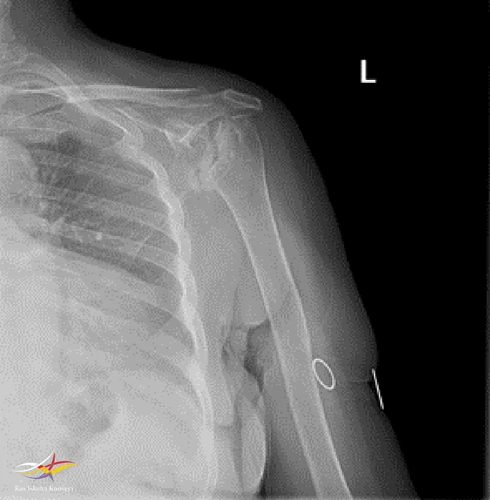

Sol Omuz MRG: Glenoidde kortikal düzensizlikler, lokalize defektif alanlar ve bu düzeyde subkondral milimetrik kistlerin eşlik ettiği medüller hafif hiperintens ödem izlenmektedir. Humerus baş kesiminde medialde de geniş bir alanda defektif görünüm mevcuttur. Buna komşu humerus başında milimetrik kistler ve medüller ödem izlenmektedir.

Humerus başında ve glenoid de osteofitik dejeneratif değişiklikler mevcuttur. Gleno-humeral eklem aralığı anterior inferiorda daralmıştır.Eklem aralığında sıvı miktarında belirgin artış izlenmedi.

Humerusta tüberkülüm majusta milimetrik kist - medüller ödem benzeri sinyal değişikliği dikkati çekmektedir.

Ön tanıda romatoid artrite bağlı eklem tutulumu, avasküler nekroz, Charcot eklemi (periferik nöropati- servikal radikülopati?) olasılıkları tartışıldı.

Hastanın ileri derecedeki eklem kısıtlılığı ve buna bağlı gelişen omuz çevresi kaslarda atrofisi olması sebebi ile artroplastiden fayda görebileceği öngörüldü.